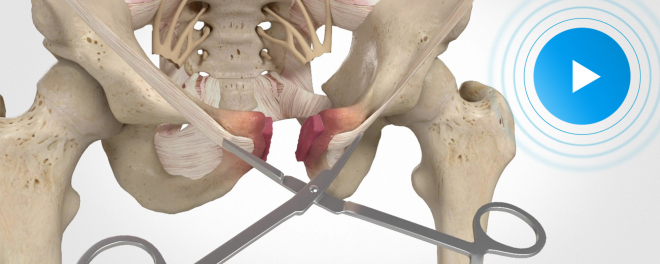

| WATCH THE VIDEO |

| Damages and Surgical Animations Aid in $4M Verdict for Motorcycle T-Bone Crash Survivor |

It was the perfect Sunday for a motorcycle ride through the streets of Anaheim, California. An inattentive driver prepared to make an unprotected left turn in an intersection. He proceeded into the path of a 35-year-old motorcyclist named Jose. Jose, an active-duty Marine, T-boned the vehicle at 35 miles per hour, ejecting himself... |

"The animation from DK Global was huge in terms of adding value to this case... I don't think we would've achieved the result that we did if not for the animation." |

| Rob Marcereau – Marcereau & Nazif |